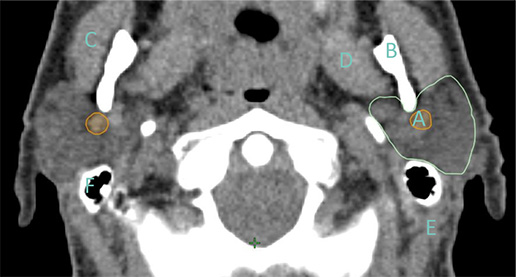

Część 1: rdzeń kręgowy, ślinianki przyuszne i krtań – wskazania dla elektroradiologów Wprowadzenie Na przestrzeni ostatnich kilku lat powstały liczne doniesienia mające na celu opracowanie wytycznych pozwalających na prawidłowe definiowanie zarówno obszarów tarczowych, jak i narządów krytycznych. W niniejszej pracy postaramy się wskazać najważniejsze z nich na przykładzie: rdzenia kręgowego, ślinianek przyusznych i krtani z uwzględnieniem anatomii narządowej, tolerancji dawek i odczynów…